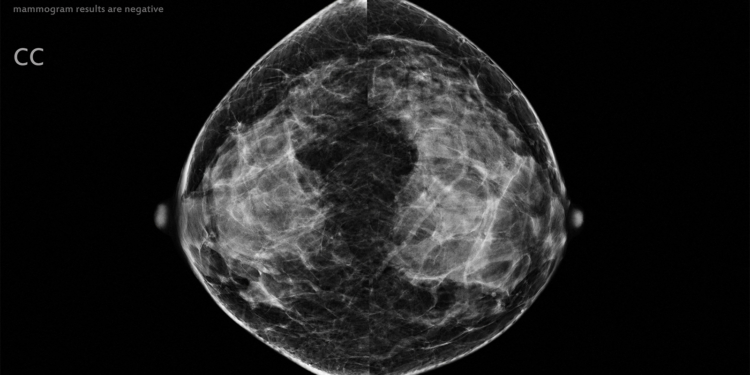

(MedPage Today) — Artificial intelligence (AI) could potentially be used to safely exclude low-risk mammograms from radiologist review, according to results from a prospective noninferiority trial.